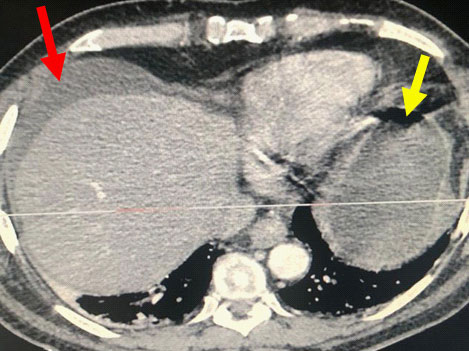

A 56-year-old male patient, who was previously healthy, was admitted to the emergency room of Hospital da Cidade – Salvador – Bahia – Brazil due to diffuse abdominal pain that started 24 hours before admission, with progressive worsening and intensity 9, on a 0-10 scale. During physical examination he was tachycardic (HR > 90 bpm), tachypneic (RR > 20), normotensive, in antalgic position and had distended abdomen with diffuse pain on decompression and poor response to opioid analgesics. He did not have systemic inflammatory response syndrome (SIRS) and laboratory tests, including white blood cell count and pancreatic enzymes were normal. The radiological routine for acute abdomen was not clarifying and thus, contrasted Computed Tomography (CT) of the abdomen was performed, showing: Free fluid in the abdominal cavity and important jejunal and gastric distension (Figures 1 & 2). The distension of the small intestine made it impossible to access the abdominal cavity by laparoscopy. Exploratory Laparotomy (EL) was performed which showed large amounts of enteric fluid in all abdominal quadrants, significant edema of the small bowel loops and multiple jejunal diverticula (Figure 3). One of them was perforated and located 30 cm from the Treitz angle (Figure 4), which was defined by segmental enterectomy of approximately 20cm (figure 5). Primary lateral-lateral anastomosis was performed using a linear stapler for intestinal reconstruction and cleaning of the abdominal cavity until clear return of the aspirate. There was a postoperative period in the intensive care unit (ICU) for 3 days, due SIRS and necessity of the clinical and laboratorial surveillance. During that time, nutritional therapy with Total Parenteral Nutrition (TPN) was started early. After improvement in abdominal distension and removal of the nasogastric tube on the 7th day after surgery (POD), an oral liquid diet without residues was introduced. There were no postoperative complications or need for surgical re-approach. Finally, the patient was discharged on the 11th POD with a mild oral diet, without complaints and with a normal bowel rhythm. There was no readmission.

Figure 1: Abdominal tomography axial section: Presence of free fluid in the abdominal cavity (Red Arrow). Gastric distension (Yellow arrow).